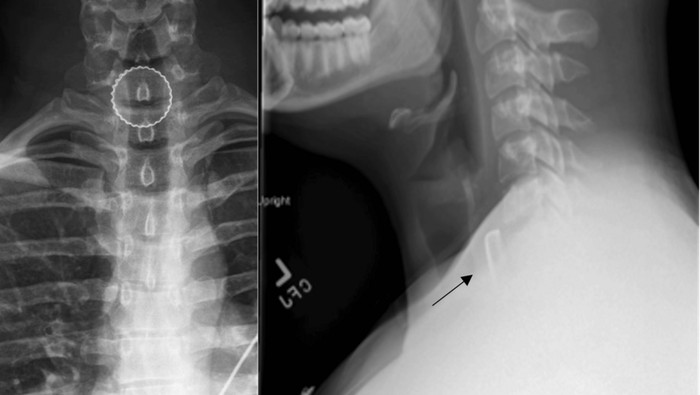

Seorang pria berusia 19 tahun di Albany, Amerika Serikat mengalami 'apes' tak sengaja menelan tutup botol besi saat bermain 'beer pong'. Karena tutup botol itu tersangkut, ia sampai kesulitan menelan dan mengalami gangguan pernapasan. (Foto: Cureus Journal)

Pemeriksaan menunjukkan tenggorokan pria tersebut mengalami peradangan. Dokter terpaksa harus melakukan operasi bedah untuk mengeluarkan tutup botol tersebut, karena berisiko memicu robekan atau perforasi (Foto: Cureus Journal)

Terungkap, ia tidak sadar tutup botol tersebut masuk ke dalam gelas tanpa sengaja. Ia tidak sadar menelannya sampai satu jam kemudian ia akhirnya pergi ke IGD Albany Medical Center. (Foto: Cureus Journal)